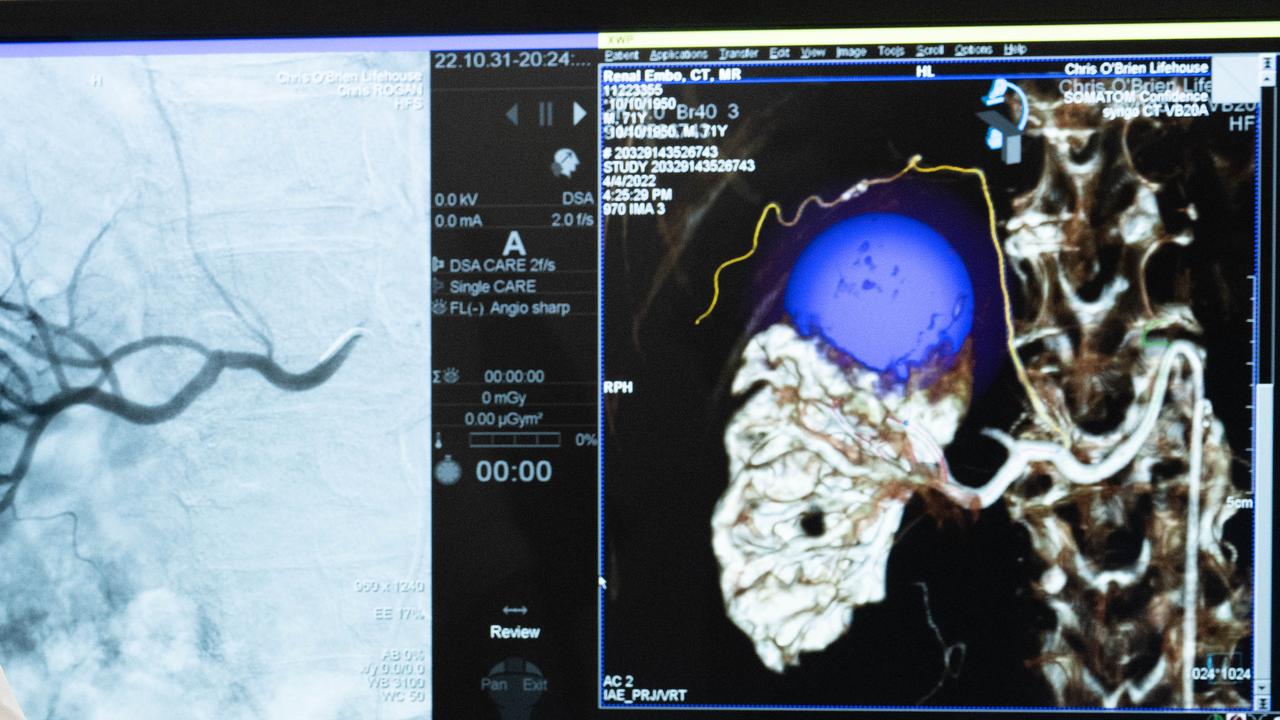

Ovarian cancer did not offer a single pathway of treatment and each patient needed to be catered to individually, Chris O'Brien Lifehouse medical oncologist Michelle Harrison said.